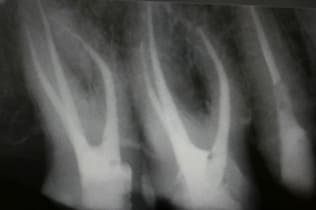

- 無症状だが、レントゲンで根の先が黒く、影が見える

根管治療は無菌の根管を作り、緊密な根管充填が絶対条件です。歯の寿命がこれで決まると言っても過言ではありません。下の写真は根管充填不良により引き起こされた、根尖性歯周炎の状態です。左が根管治療前、右が根管充填後のレントゲン写真。

根管治療をしないと抜歯になるかも!?

この病巣を根管治療しないで放っておくと、最悪のケースとしては抜歯も余儀なくされます。根管治療は皆様の歯を残すうえでは非常に重要な治療となってきます。